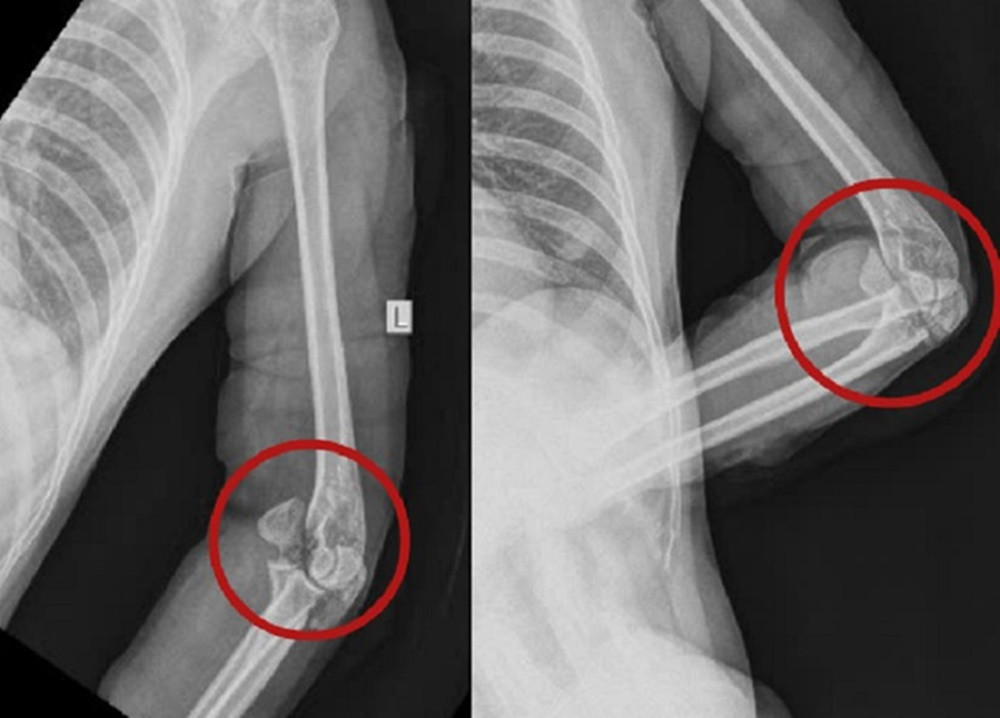

Theo BS Quang Nhật, khi tiếp nhận, qua thăm khám, chẩn đoán hình ảnh, các bác sĩ ghi nhận, vùng vai, cánh tay, cẳng tay, bàn tay cả hai bên của nạn nhân có nhiều vết thương dài và sâu, lộ gân, đứt cơ. Vùng khuỷu trái bị vết chém chí mạng gây gãy xương mỏm khuỷu, gãy xương lồi cầu trong xương cánh tay, lộ khớp khuỷu trái.

Cuộc mổ cấp cứu đã giúp bệnh nhân vượt qua nguy kịch. Sau cuộc mổ thứ nhất, bệnh nhân được chăm sóc hậu phẫu ổn định. Các bác sĩ đã thực hiện cuộc mổ thứ hai kết hợp xương mỏm khuỷu, lồi cầu trong bằng nẹp vít cho bệnh nhân. Hiện sức khỏe của người bệnh đã bình phục tốt.